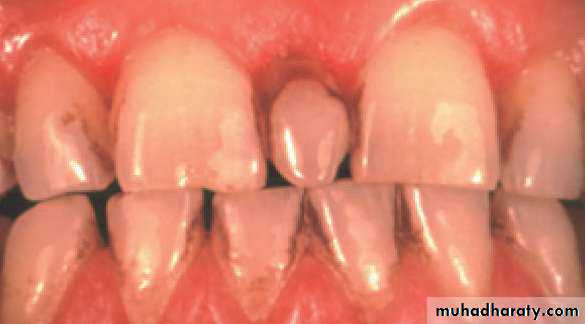

• Mesiodens :When they occur between the maxillary central incisors.

• Common region of the jaws to be affected is the premaxilla.

Mesiodens

Many supernumerary teeth never erupt, but they may delay eruption of nearby teeth or cause other dental problems.

If they erupt, they can cause malalignment of the normal dentition.